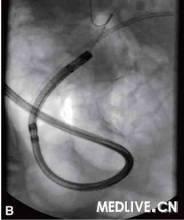

4.子鏡送達十二指腸後,兩位醫師協同操作,與ERCP一樣將子鏡插入膽管內。注意儘量不用抬鉗器抬起子鏡,以免損傷子鏡導光纖維。子鏡進入膽管後,母鏡操作者主要是進行子鏡的插入、後退及轉動母鏡,協助子鏡進到合適的部位;子鏡操作者則可利用子鏡的角度鈕使子鏡處於最有利於各種檢查和治療的位置。子鏡進入膽總管後,可以深入至肝總管、膽囊管開口,如膽管擴張明顯,還可能送達一、二級肝管分支,偶爾可通過擴張的膽囊管進入膽囊。